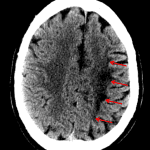

- Areas of low attenuation in the left frontoparietal white matter

- Watershed territory infarct

Areas of low attenuation in the left frontoparietal white matter in a distribution most suggestive of ACA/MCA watershed territory ischemia. No significant associated mass effect or evidence of hemorrhagic transformation.